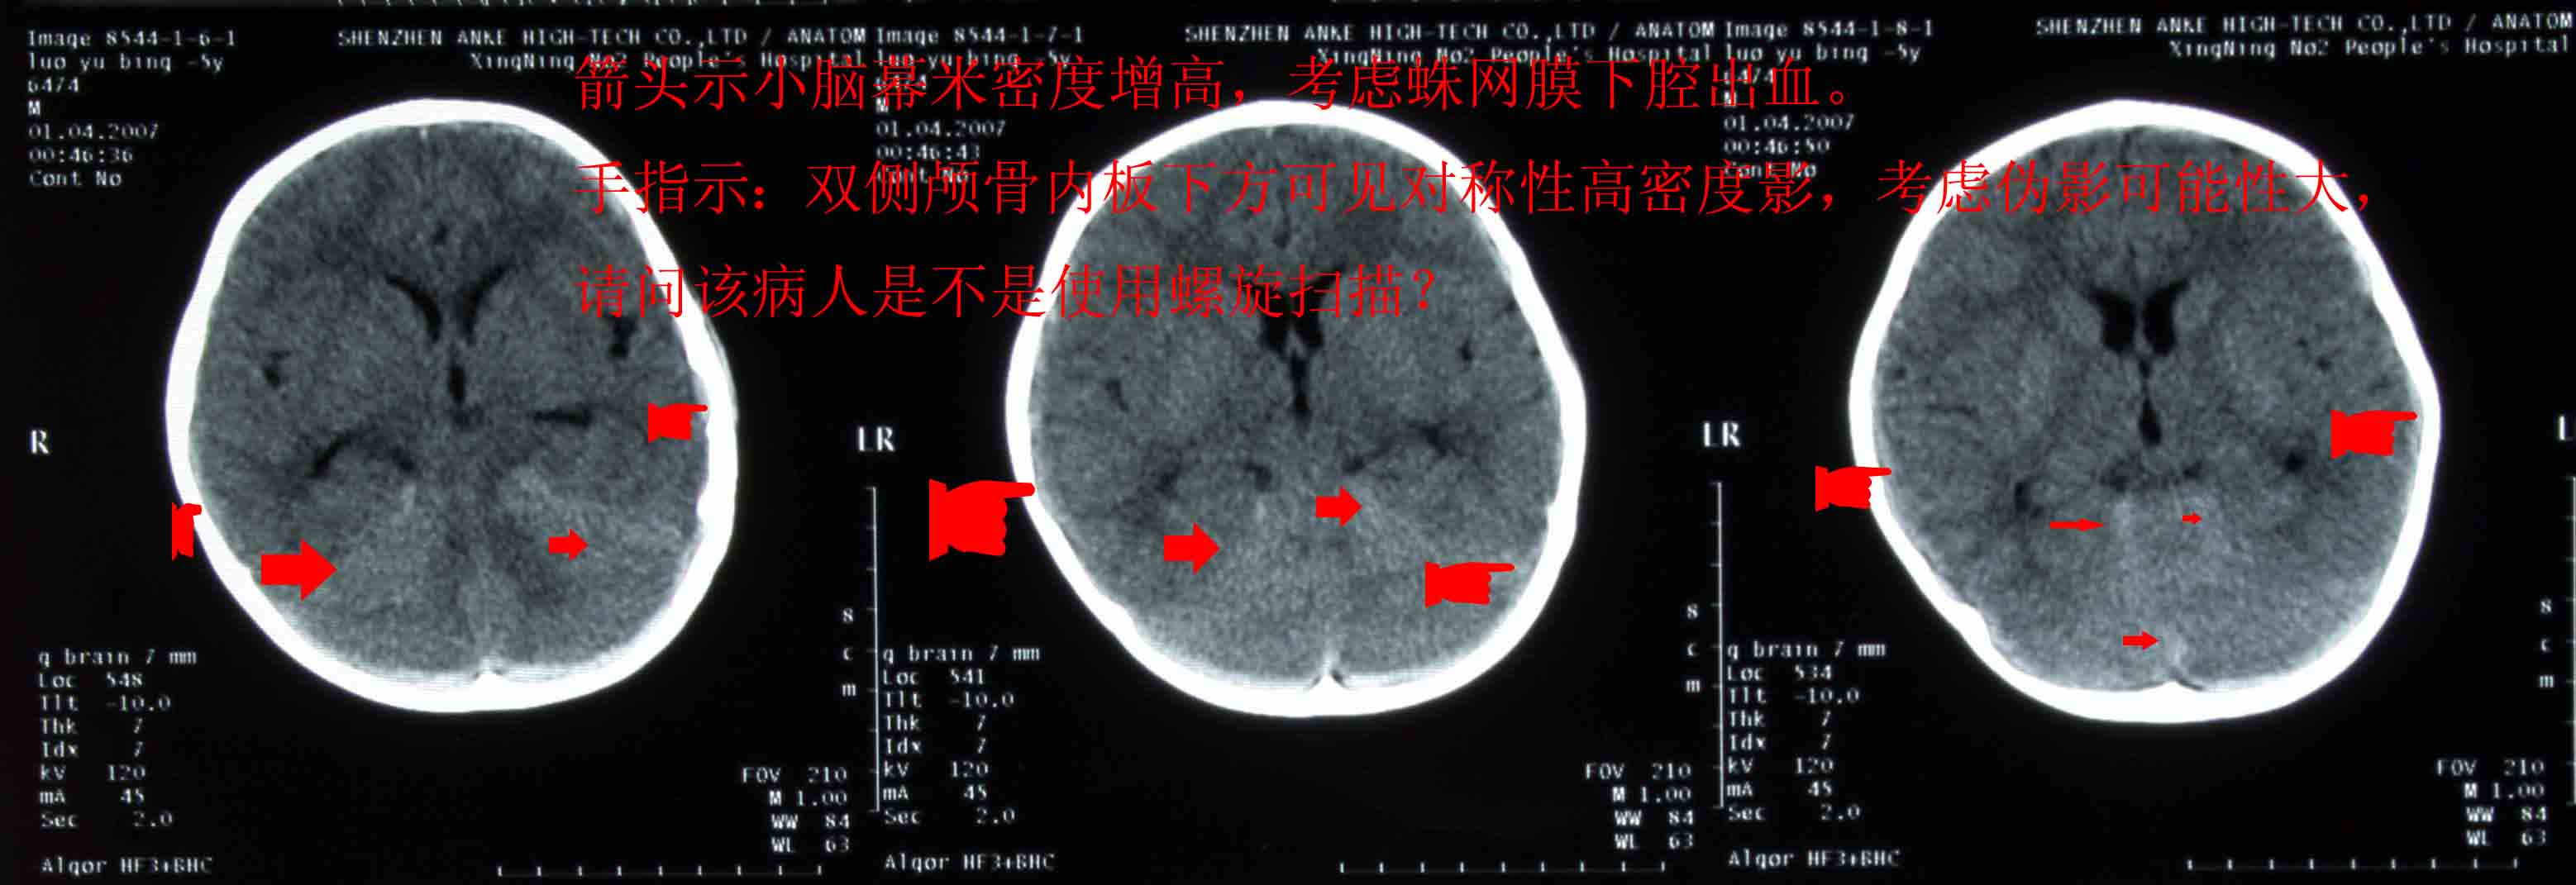

患儿,男,3周岁,半小时前不慎从床上摔下来,当时前额着地,后诉有点痛,伴呕吐二次,请各位老师会诊,患儿头颅有没有问题,后枕部颅下密度增高影,是伪影还是有出血,请指点:

图处箭头示的地方是出血吗,请指点

支持后颅窝少量蛛网膜下腔出血。

后颅窝蛛网膜下腔出血。

小脑幕区蛛网膜下隙出血

支持小脑幕区少量蛛网膜下腔出血。我最近也遇到两例这样的病例,我们一直讨论为此诊断。

不是螺旋扫的,现在患儿没有其它不适.